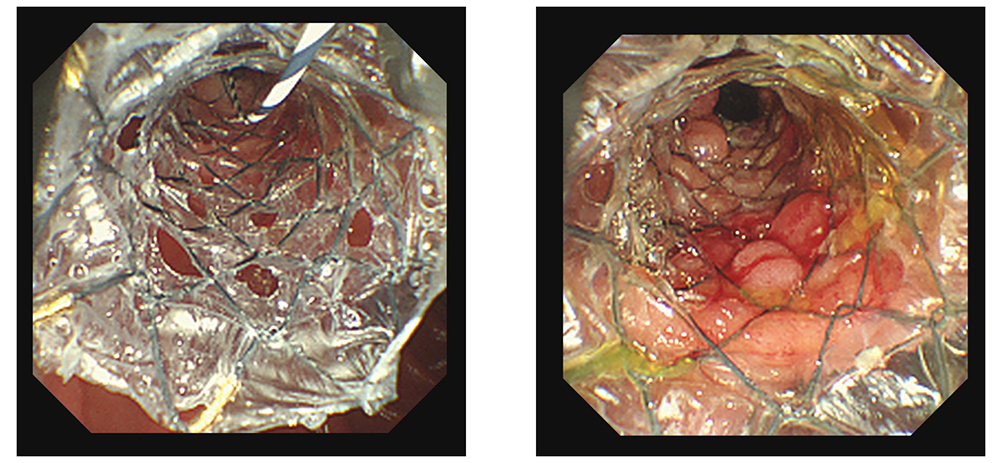

臨床画像

留置前後の臨床画像

| 画像提供: | 順天堂大学医学部附属順天堂医院 伊佐山 浩通 先生 順天堂大学医学部附属練馬病院 高橋 翔 先生 |